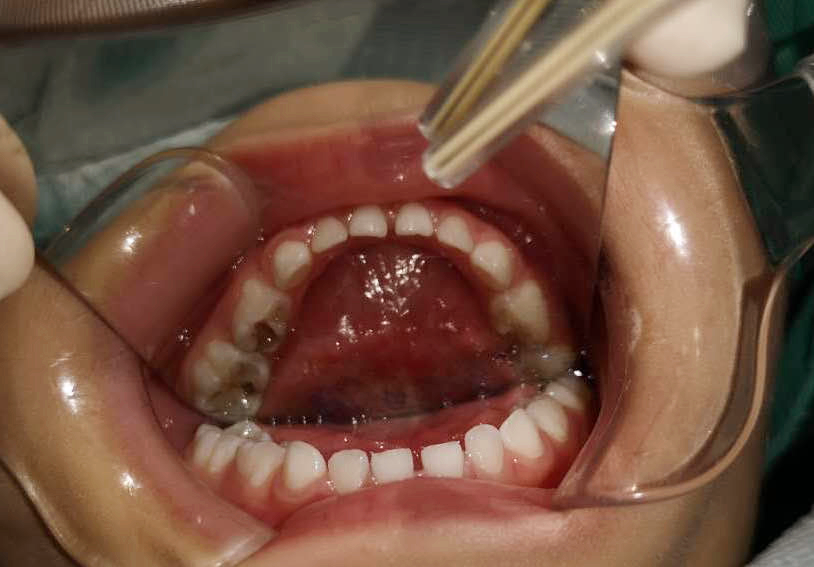

調(diào)節(jié)前

調(diào)節(jié)后